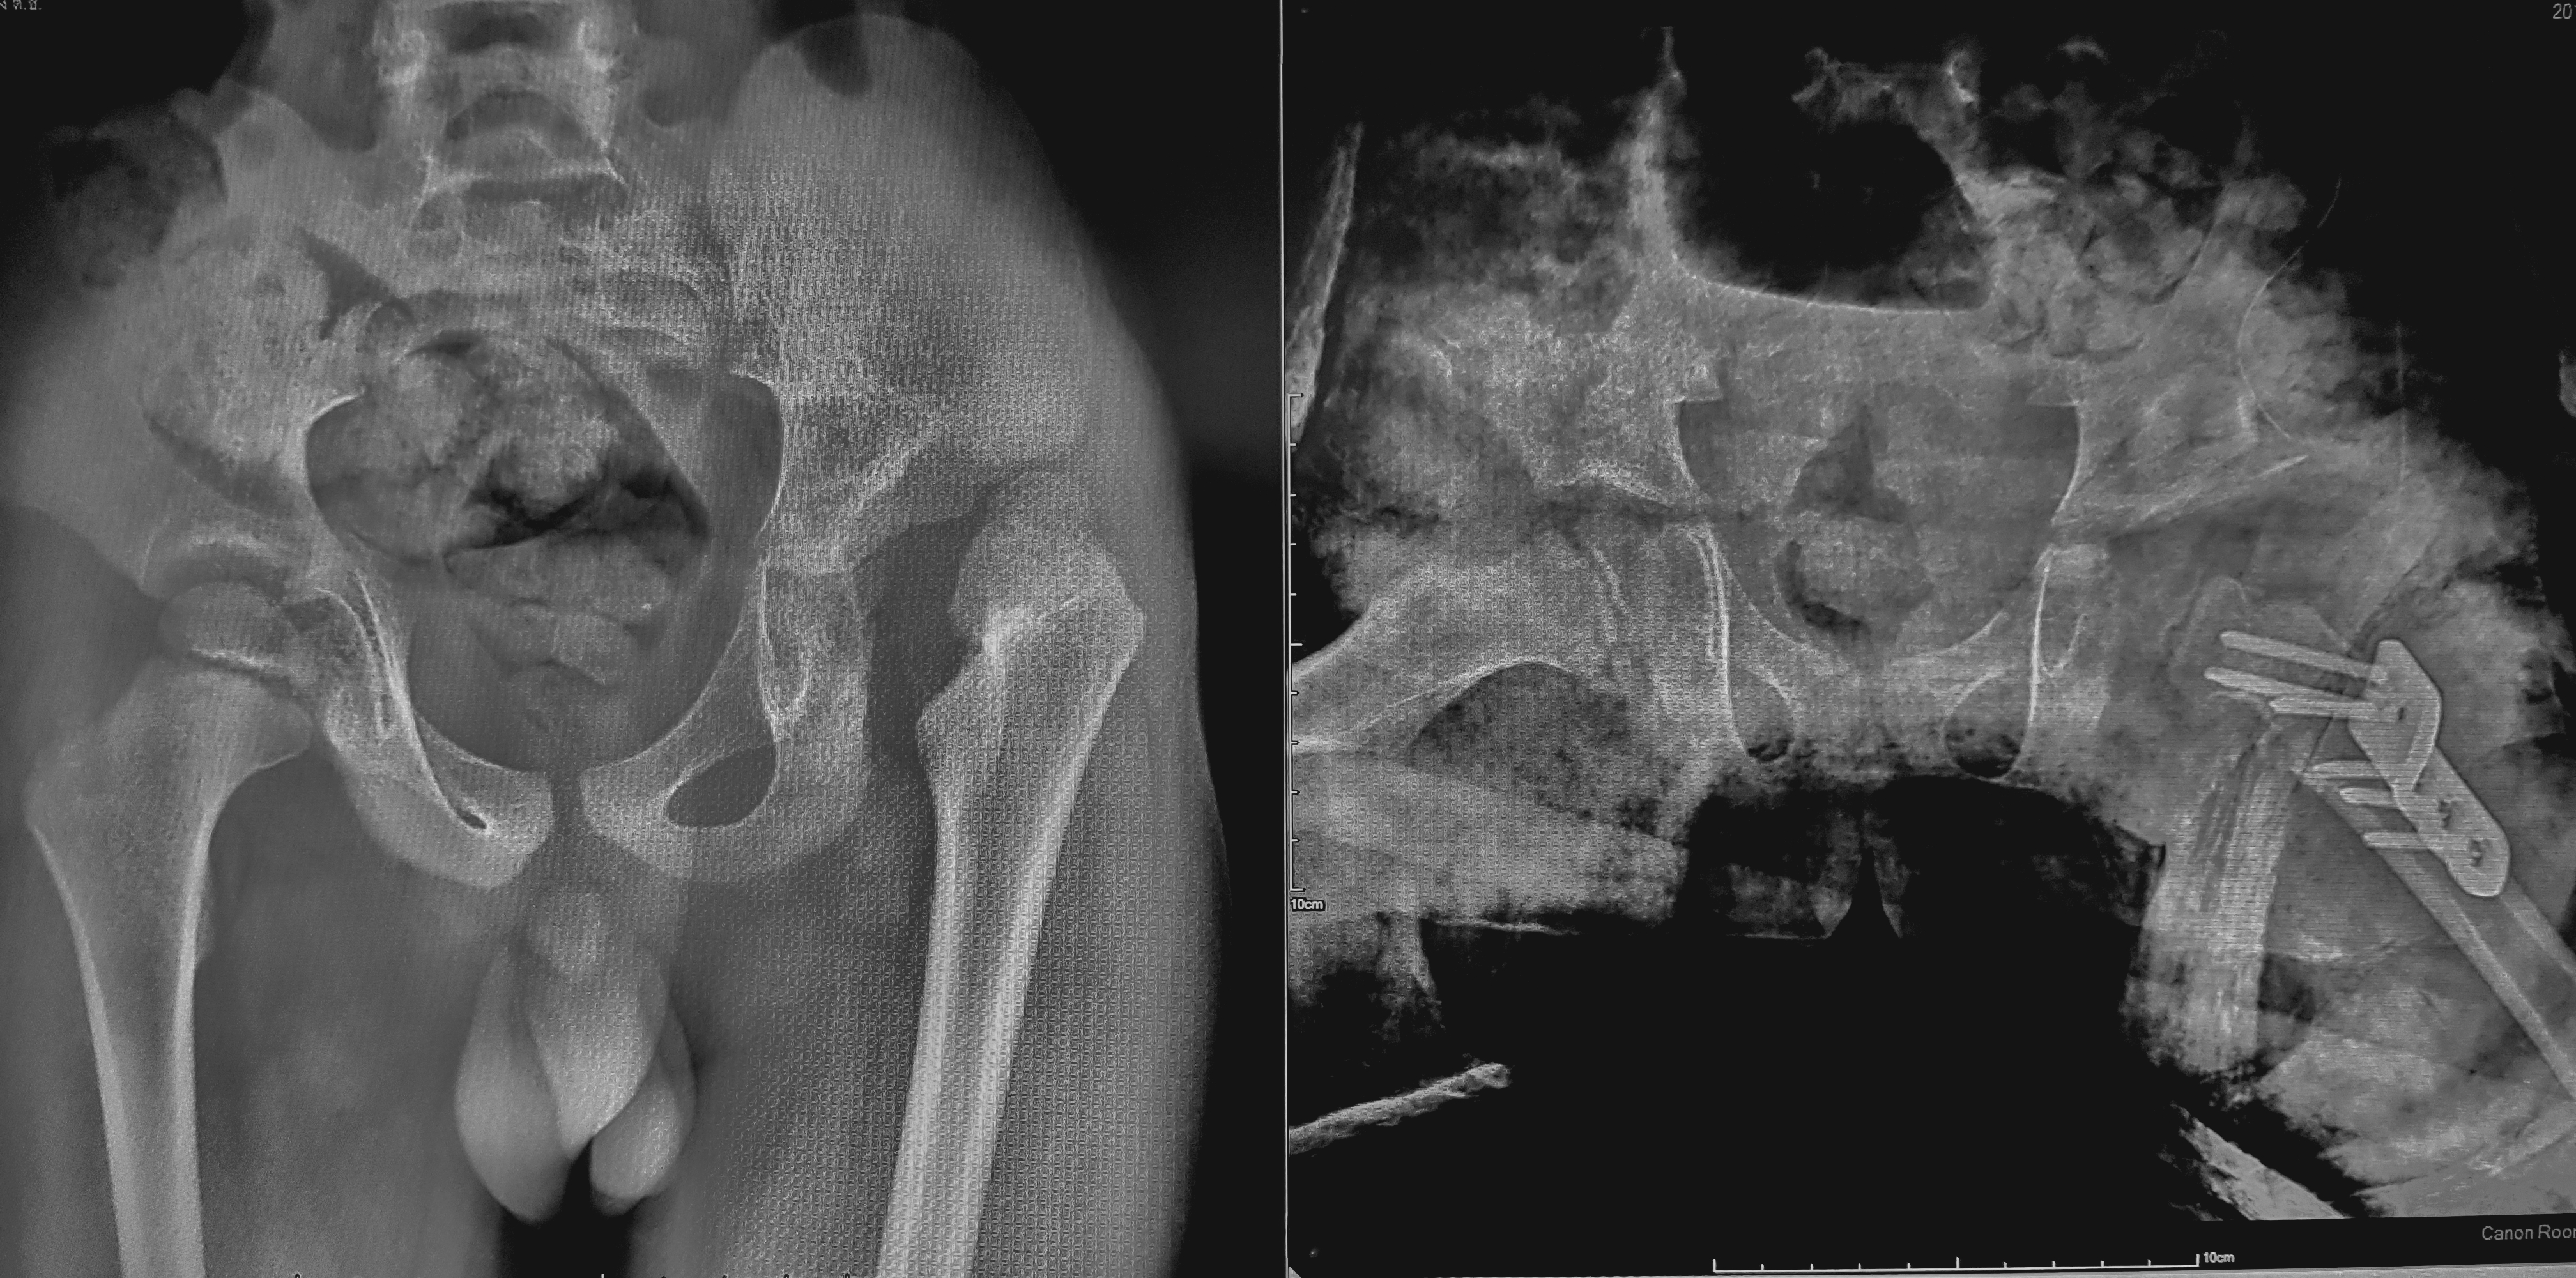

Normal Variants refer to skeletal conditions that are altered within the normal range, and Congenital Abnormality refers to congenital skeletal variations. Although there are variations that do not cause clinical problems, some types (especially congenital abnormalities) can be important factors in causing musculoskeletal pain, and some of them can be contraindications for manual therapy.

The most important thing to be careful about in manual therapy is contraindications. Therefore, this course is an essential subject that all manual therapy specialists must study without exception, as it can prevent side effects from manual therapy by identifying skeletal deformation through x-ray images, and it is a field that is strongly recommended as a prerequisite for manual therapy technique subjects.

The skeletal deformation of the musculoskeletal system can be accurately diagnosed through x-ray. Therefore, side effects that may occur during manual therapy can be prevented in advance, and the indications, contraindications, and target of manual therapy can be clearly recognized.